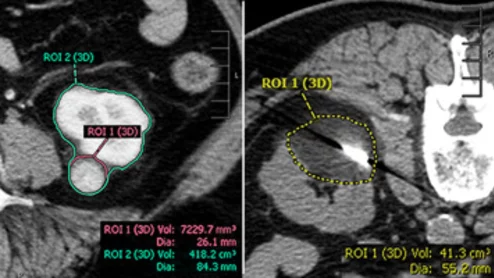

renal cryoablation volumes

A paper in the Journal of Vascular and Interventional Radiology offers new guidance on how ablation volumes affect renal function in solitary kidneys and highlights ranges that pose the least risk to patients.